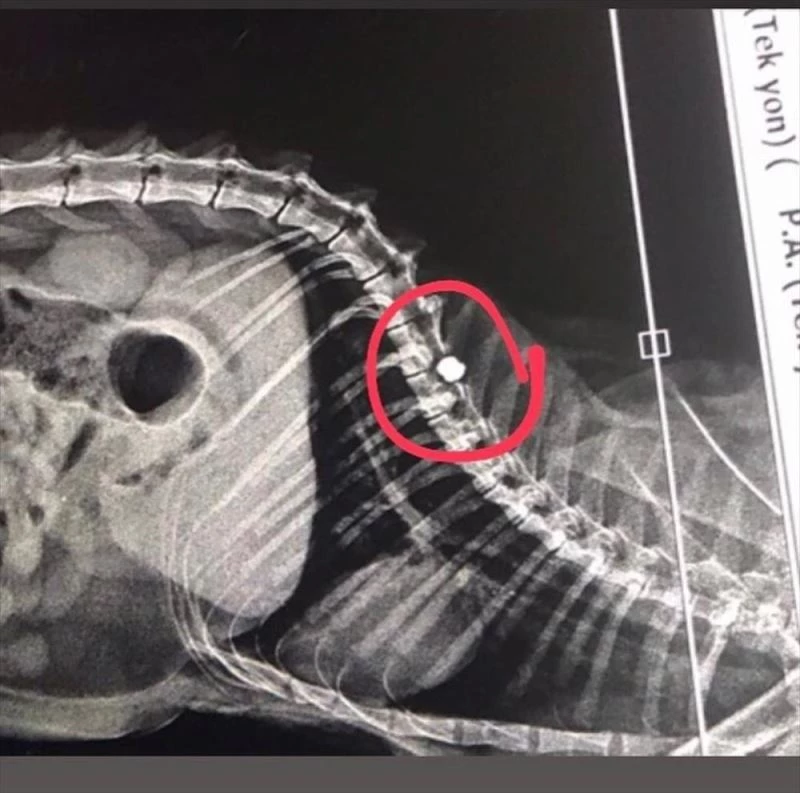

ADANA (AA) - Adana'nın Kozan ilçesinde havalı tüfekle vurulması sonucu felç kalan kedi, kendisini bulan kişi tarafından sahiplenildi.

Tufanpaşa Mahallesi Gül Sokak'ta Atakan Kızıldağ, yolda hareketsiz halde bir kedi gördü. Kızıldağ, yaptığı incelemede bel kısmından yaralı olduğunu gördüğü kediyi veterinere götürdü.

Burada yapılan muayenede kedinin havalı tüfekle vurulmuş olduğu belirlendi.

Olay nedeniyle felç kalan kedi, kendisini bulan Atakan Kızıldağ tarafından sahiplenildi.